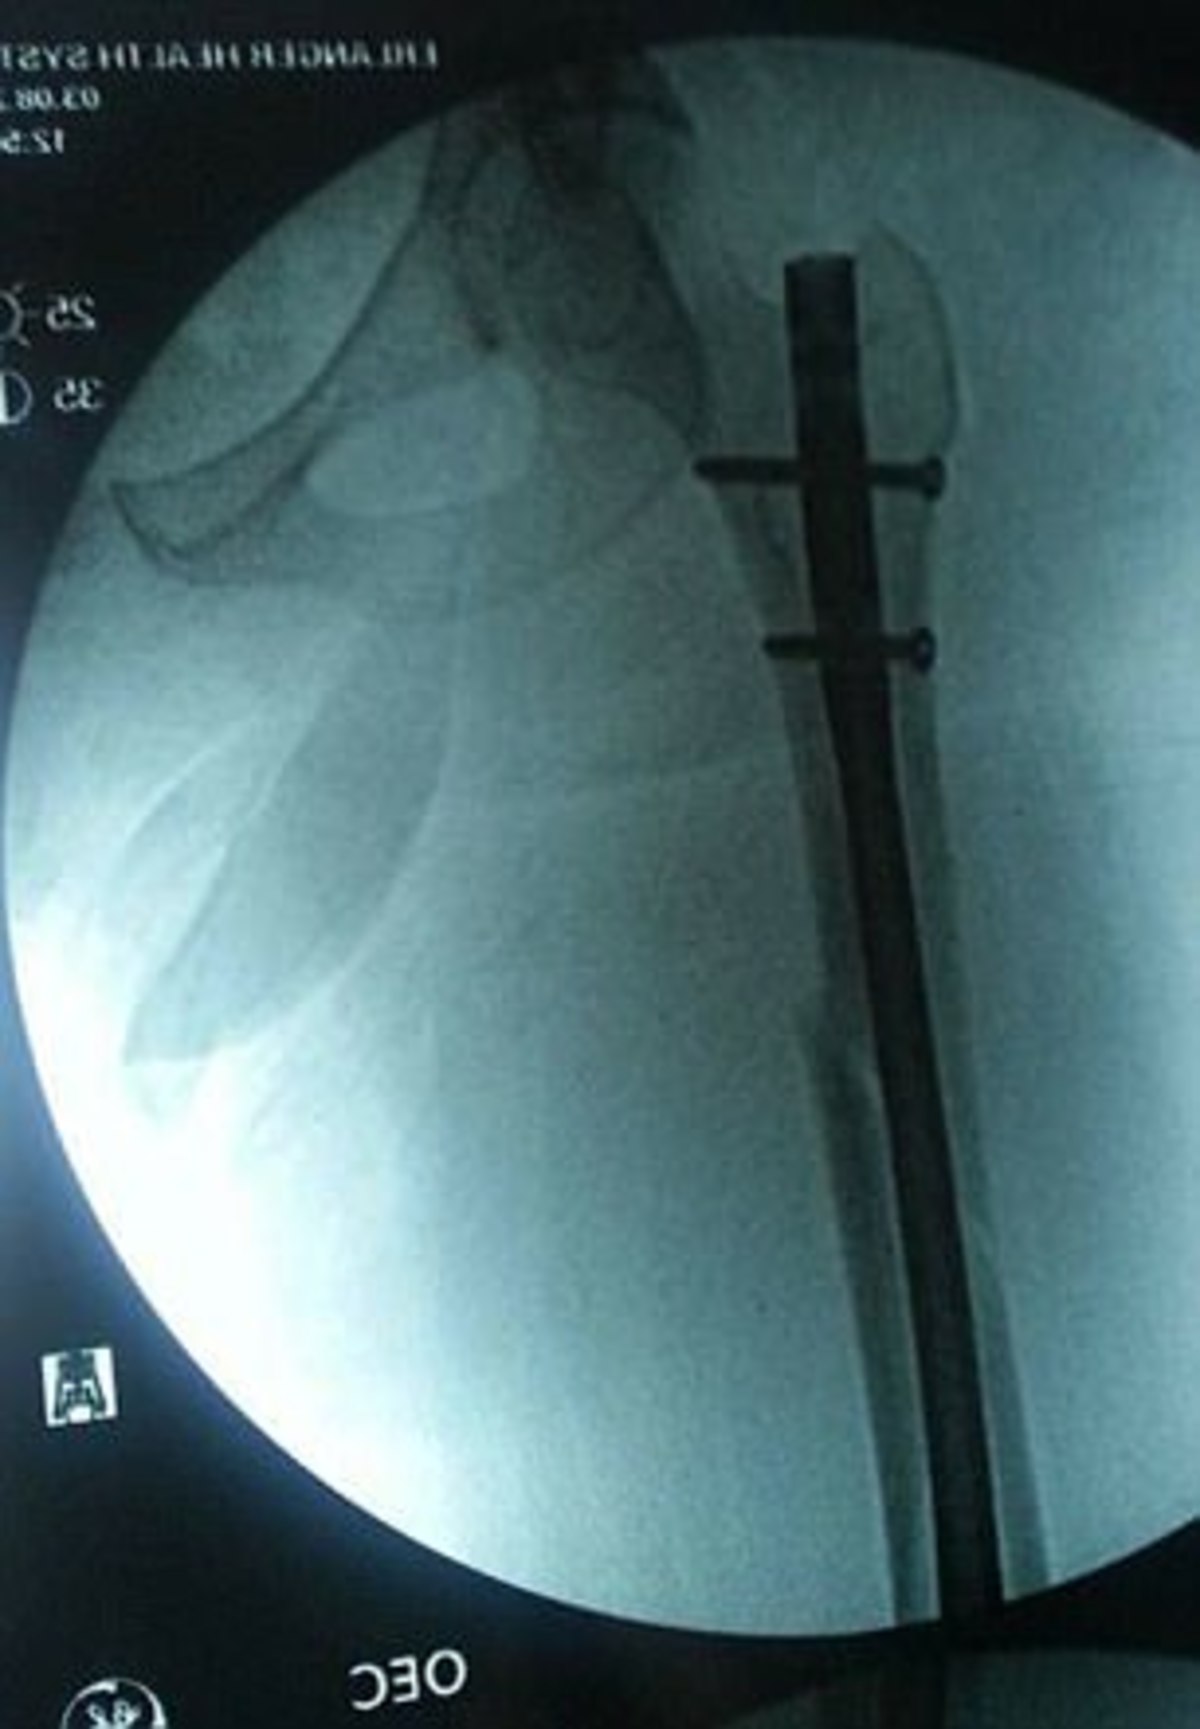

Ο οδηγός και το παιδί είχαν μόνο γρατζουνιές και μώλωπες, αλλά ο αερόσακος «εκτίναξε» το πόδι της Audra προς το πρόσωπό της, σπάζοντας τη μύτη της και μαζί τον αστράγαλο και τον μηρό της σε τέσσερα σημεία!

Σήμερα, ζει με δύο βίδες στον αστράγαλο της, δύο στο ισχίο της, και δύο στο γόνατό της, και δεν μπορεί να σταθεί περισσότερο από τέσσερις ώρες την ημέρα.